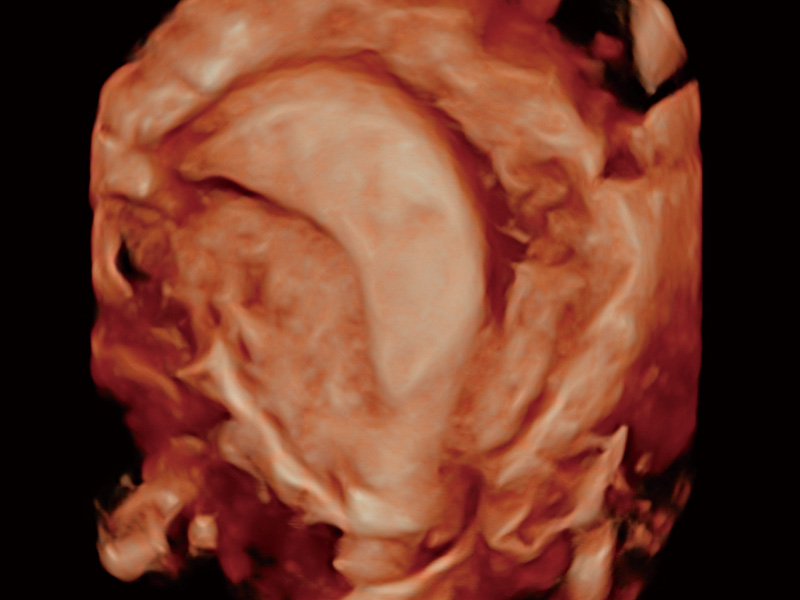

“生育问题”即关系民族复兴,也关系亿万家庭的幸福。随着婚育年龄推迟、社会压力增加等因素,越来越多人群也面临着“生不出、生不好”的问题。辅助生殖作为治疗不孕不育最有效的方法之一,也逐渐成为育儿新希望。而超声检查能为生殖需求人群的初诊评估提供宝贵的信息。 P20 Elite是球速体育入口匠心打造的一款生殖应用型彩超。她继承球速体育入口高端极光平台,突破性地将多款新型芯片及硬件模块进行整合,均衡了高端系统性能与小巧灵动机身。P20 Elite卓越的图像质量搭载专科探头,旨在为您提供全面的辅助生殖解决方案。

P20 Elite配备了丰富的生殖探头群和临床应用功能,在卵泡监测、穿刺取卵、胚胎移植、妊娠确认等领域,为生殖需求人群提供了新的临床机会,重新定义高端超声如何应用于生殖健康检查。